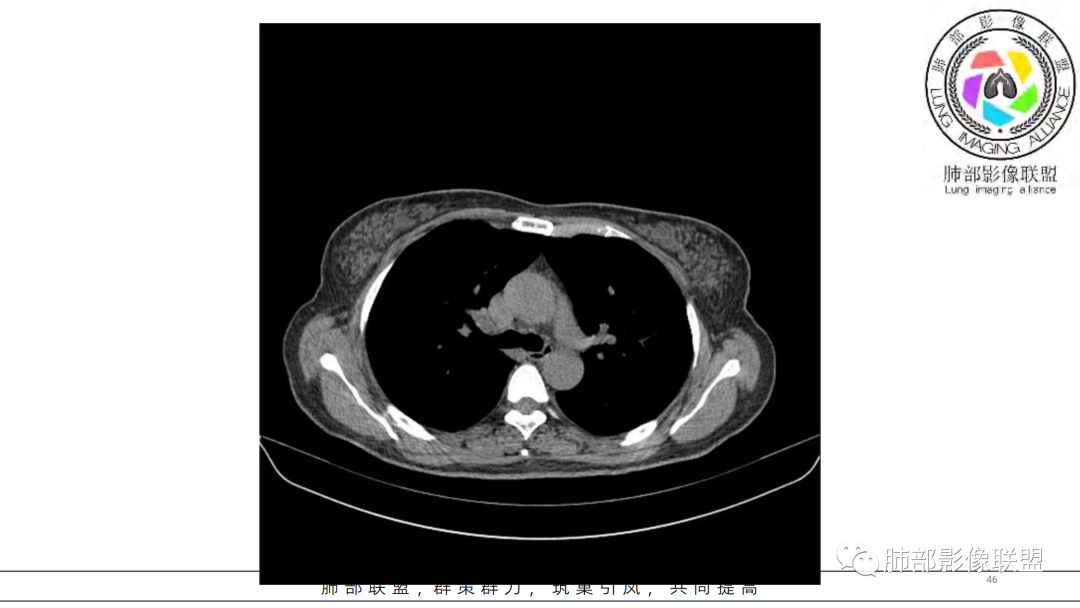

2.右肺下叶及中间段支气管后方类圆形块影,边界较清楚,未见分叶及毛刺,病灶部分突入支气管腔内(冰山一角),局部管腔狭窄,相应肺叶未见片影或体积变化。

3.块影密度均匀,未见液化坏死及钙化,渐进性强化,强化显著。

4.双肺门及纵隔未见增大淋巴结。未见胸腔积液。